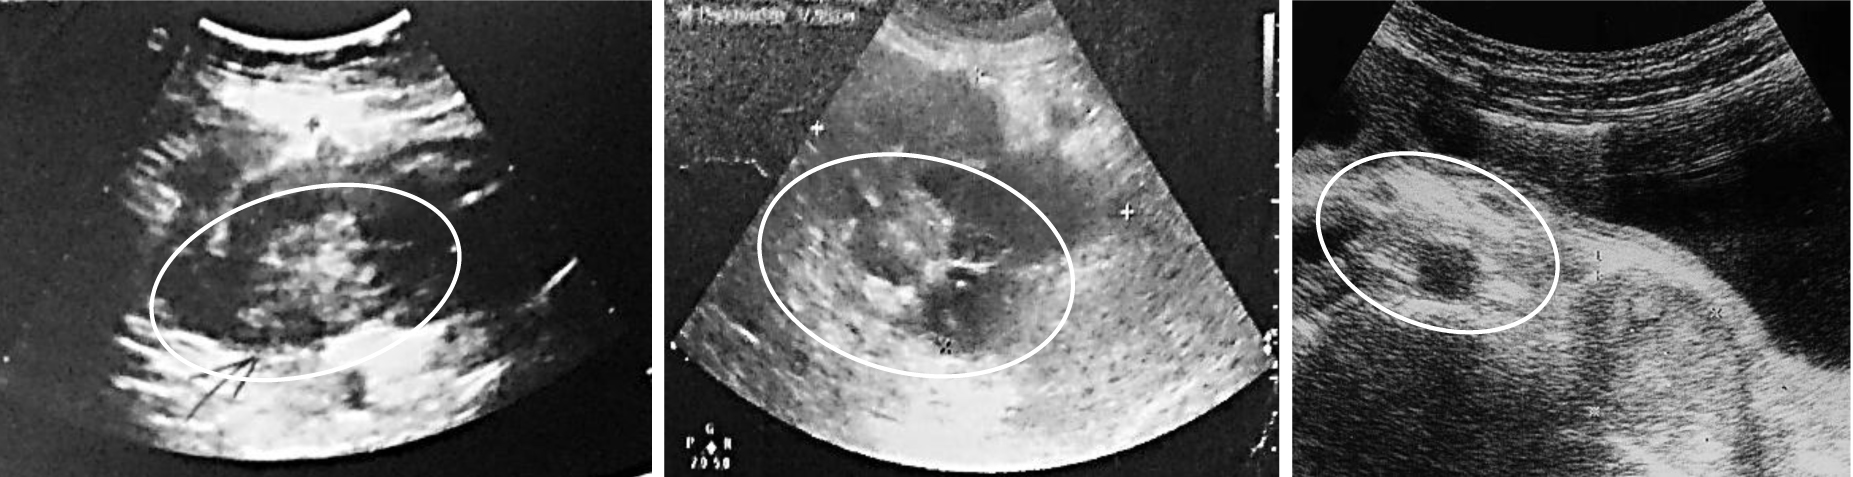

Капсульная энтероскопия [13], проведенная 4 больным, позволила визуализировать патологический очаг, провести оценку гемостаза и определить характер роста опухоли (рис. 4).

Рис. 4. Капсульная энтероскопия: а) продолжающееся кровотечение из подслизистого образования; б) фиксированный сгусток в просвете кишки; в) экзофитная опухоль